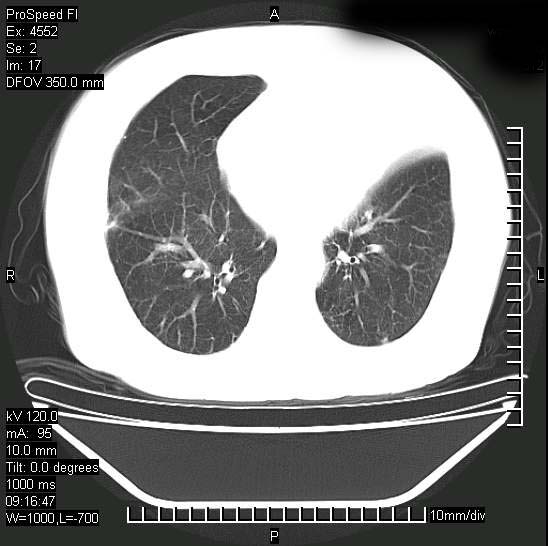

标题: CT15528:女性,79岁,近几日晚上高热,39度,仍咳少量血

十几年前曾患肺结核,一周前突咳血约100ml,中性粒细胞稍高,诊断两上肺陈旧结核,下肺炎症,给予抗炎治疗,近几日晚上高热,39度,仍咳少量血,4天前ct及今天ct上传。

今天ct

短短几天内,病变范围明显增多扩大,以左侧明显,而且双侧出现胸水,还是考虑感染.

短短几天内,病变范围明显增多扩大,以左侧明显,而且双侧出现胸水,我更多考虑左侧中心性肺癌并并阻塞性不张及肺炎,炎症变化也太快了!